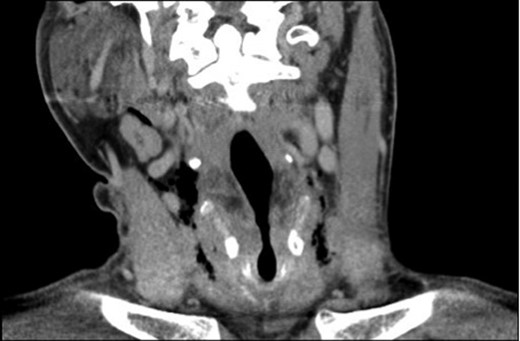

A 39-year-old male patient with a background of type II diabetes, spina bifida and meningocele hydrocephalus presented to the emergency ENT clinic with a 2-day history of a throat complaint. He described that while hyperextending his neck to finish his cup of coffee he felt a sudden crack in the middle and central portion of his throat. This crack produced a sound that was also heard by his partner on the other side of the room. The patient subsequently experienced a spontaneous coughing fit. During the history, he described pain over the thyroid cartilage, odynophagia, pain on moving his neck and a hoarse voice. He also described the sensation of having something flapping in his throat while breathing. He denied any recent history of throat trauma and had no other ENT complaints. On examination he had a tender thyroid cartilage with palpable crepitus of the thyroid cartilage when balloting it between the fingers of each hand. There was no palpable surgical crepitus of the soft tissues of the neck and no lymphadenopathy. Flexible fibre optic nasendoscopy allowed dynamic and real-time evaluation of the vocal cords and revealed significant bruising and swelling of the right arytenoid cartilage. Potential cord avulsion or paralysis was not identified. A computed tomography (CT) scan was subsequently arranged to further assess the laryngeal anatomy and was reported to show locules of free air in the soft tissues of the neck with generalized oedema of the paraglottic tissues (Fig. 1). There was no fracture of the cartilage. The patient was admitted for strict airway observation, given a stat dose of IV steroid and started on IV antibiotic to cover supraglotittis. Blood biochemistry and haematology samples were normal, with the exception of the C-reactive protein (a marker of inflammation), which was 58 mg/l. Repeat nasendoscopic examination the following day showed that the bruising had migrated into the right vocal fold and a new fullness in the left pyriform fossa. By Day 3 following admission the nasendoscopic examination was improving to normal and the right arytenoid cartilage was seen to be less floppy. By this time the patient's pain was settling, although the hoarseness of voice was still present. He was discharged with 7 days of oral antibiotics and was reviewed in ENT clinic at 1 week where, although his voice was still hoarse, the nasendoscopic examination was normal. By 6 weeks, the voice had settled, the thyroid cartilage crepitus was gone and the larynx had returned to normal.